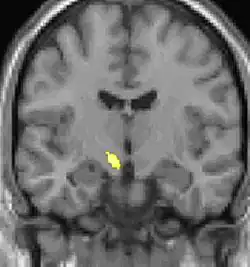

| Positron emission tomography (PET) shows brain areas being activated during pain. | ||

| Voxel-based morphometry shows brain area structural differences. | ||

Positron emission tomography (PET) scans indicate the brain areas which are activated during attack only, compared to pain free periods. These pictures show brain areas that are active during pain in yellow/orange color (called "pain matrix"). The area in the center (in all three views) is activated only during cluster headaches. The bottom row voxel-based morphometry shows structural brain differences between individuals with and without CH; only a portion of the hypothalamus is different.[36]